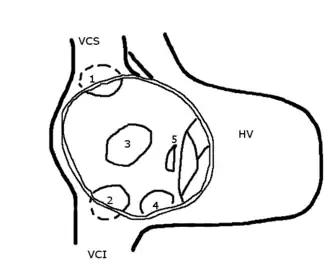

Le défaut de fermeture peut être situé :

- à la partie antérieure du septum interatrial, voire s'étendre sur le septum interventriculaire (canal atrio-ventriculaire). Elle prend alors le nom de communication de type ostium primum (5) et correspond à environ 15 % des cas découverts chez l'adulte[2] ;

- au milieu du septum interatrial, au niveau du foramen ovale. Ce sont les CIA de type ostium secondum, de loin les plus fréquentes (75 % chez l'adulte) (3);

- à la partie haute de la cloison, à proximité de l'abouchement de la veine cave supérieure ; communication de type sinus venosus qui est toujours associé à un retour veineux pulmonaire droit anormal (1) : 10 % chez l'adulte.

- à la partie basse de la cloison, à proximité de la veine cave inférieure et du sinus coronaire (proche du retour veineux des vaisseaux du cœur ou coronaires) (4).